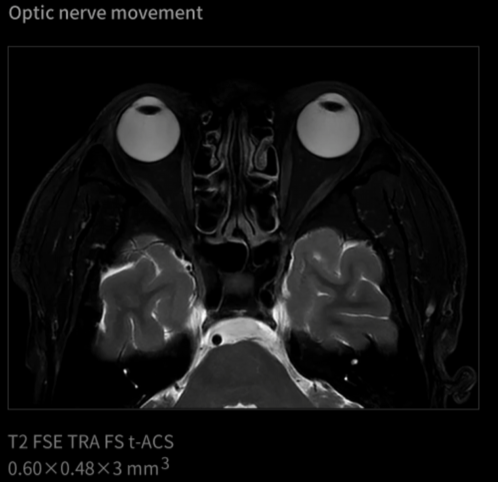

Od vzniku magnetické rezonance je pohyb jednou z největších výzev při zobrazování. Celá desetiletí byly v tomto odvětví zkoumány různé technologie pro „zmrazení pohybu“. Inovace uMR Ultra dnes slibuje svět MRI bez omezení pohybu – oblast, ve které můžeme pozorovat skutečný stav lidského těla. Jelikož otevíráme novou dimenzi zobrazování pomocí MR, je komplexní transformace diagnostických standardů nevyhnutelná.

UMR Ultra je vybaven nejmodernější technologií, která poskytuje výjimečné zobrazovací schopnosti a zaručuje přesné a konzistentní výsledky v širokém spektru klinických aplikací. Jeho pokročilý zobrazovací systém nabízí jasnost a přesnost od hlavy až po paty a tvoří základ spolehlivé diagnózy. Zařízení uMR Ultra, podporované nejmodernějším hardwarem a inovativním softwarem, zlepšuje klinické pracovní postupy a přispívá k průlomovým objevům i ke zlepšení péče o pacienty.